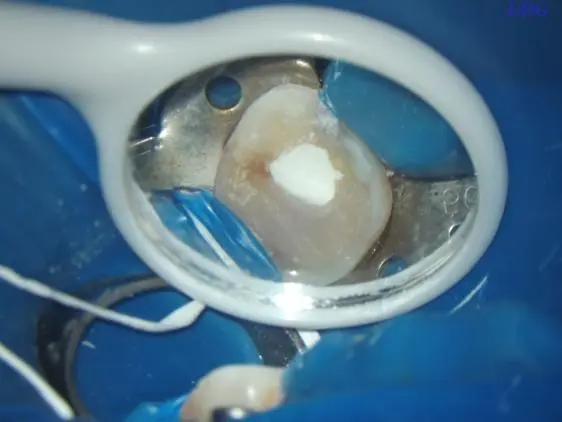

“大夫,快帮我止痛,真的受不了!”25岁的曹女士捂着左脸冲进西安市红会医院口腔科,眼泪在眼眶里打转。原来两周前她在当地医院“补牙”,三天前突然跳痛,彻夜未眠。经过详细问诊、临床探查及数字化X光片比对,医生迅速给出诊断:左上第一磨牙慢性牙髓炎急性发作。“别担心,…